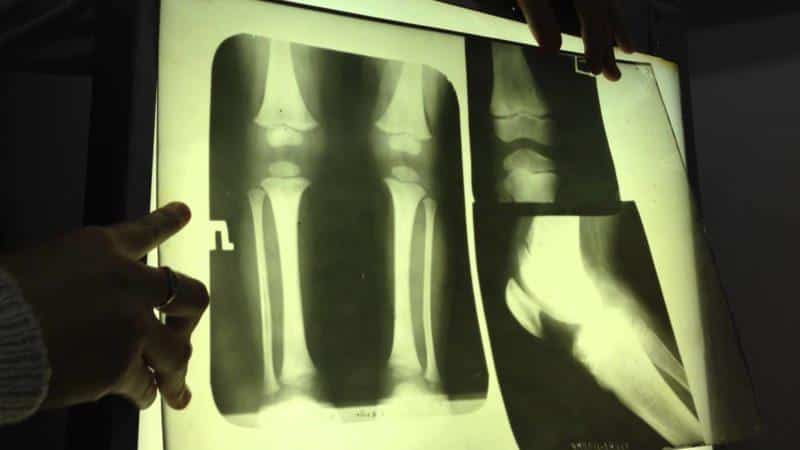

Для того чтобы выяснить причины болей в тазобедренном и коленном суставах, необходимо провести детальное медицинское обследование. Поскольку симптомы различных заболеваний могут быть схожи, по начальным признакам невозможно точно установить диагноз и начать полноценное лечение. Специалисты могут рекомендовать следующие виды исследований:

- магнитно-резонансную томографию;

- артроскопию;

- рентгенографию;

- биохимический анализ крови.